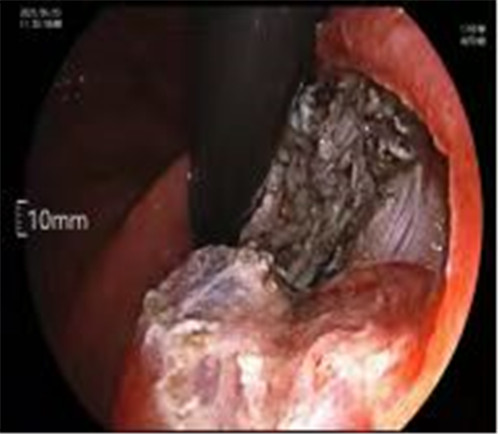

近期病例之一,圖片依次為:胃鏡、超聲胃鏡、ESE術(shù)中、術(shù)后、切下病變。

通過(guò)內(nèi)鏡切開(kāi)瘤體表面粘膜,分離后挖除瘤體,或以消化道全層切除的方法切除瘤體,并在內(nèi)鏡下縫合切口。與傳統(tǒng)手術(shù)相比,該項(xiàng)技術(shù)利用了人體自然通道,不會(huì)破壞人體結(jié)構(gòu),更加微創(chuàng)。不超過(guò)3cm向消化道腔內(nèi)生長(zhǎng)為主的良性或低度惡性粘膜下腫瘤(如間質(zhì)瘤、類癌、平滑肌瘤等),都可采用ESE治療。